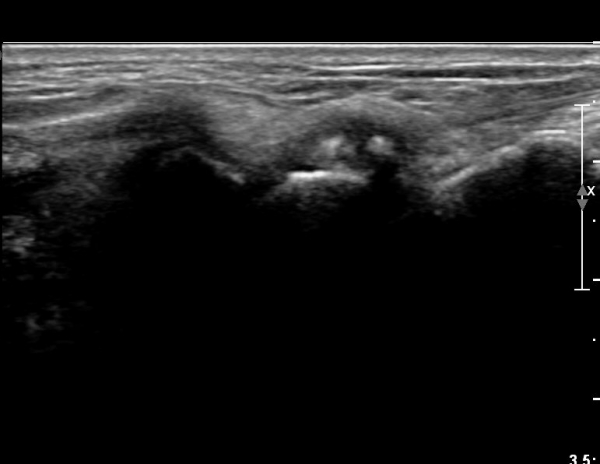

¼Õ¸ñ Ⱦ´Ü¸é°Ë»ç»ó ÁÖ»ó°ñ¿ù»ó°ñ Àδë´Â Á¤»óÀûÀ¸·Î °üÂûµÇ³ª ¿ù»ó°ñ»ï°¢°ñ ÀÎ´ë ºÎÂøºÎ

¿ù»ó°ñ ÇÇÁú°ñÀÇ ºÒ±ÔĢȭ¿Í »ï°¢°ñ Ç¥ÃþÀÇ °ñÆíÀÌ °üÂûµÈ´Ù(»çÁø 3).